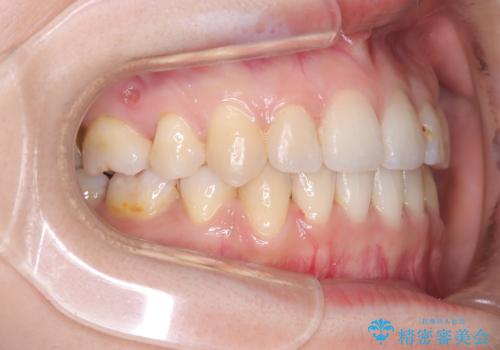

- 主訴:口元を下げて前突感を無くしたい、下の歯の凹凸も無くしたい

右側第二小臼歯、左側第一小臼歯、下顎両側第一小臼歯を抜歯しワイヤ-矯正を行いました。

骨格的顎の変位を認めたため、顔貌に対しピッタリ上下の歯の正中を合わせることは難しいと説明し、上下左右計4本小臼歯を抜歯しワイヤー矯正治療を行いました。